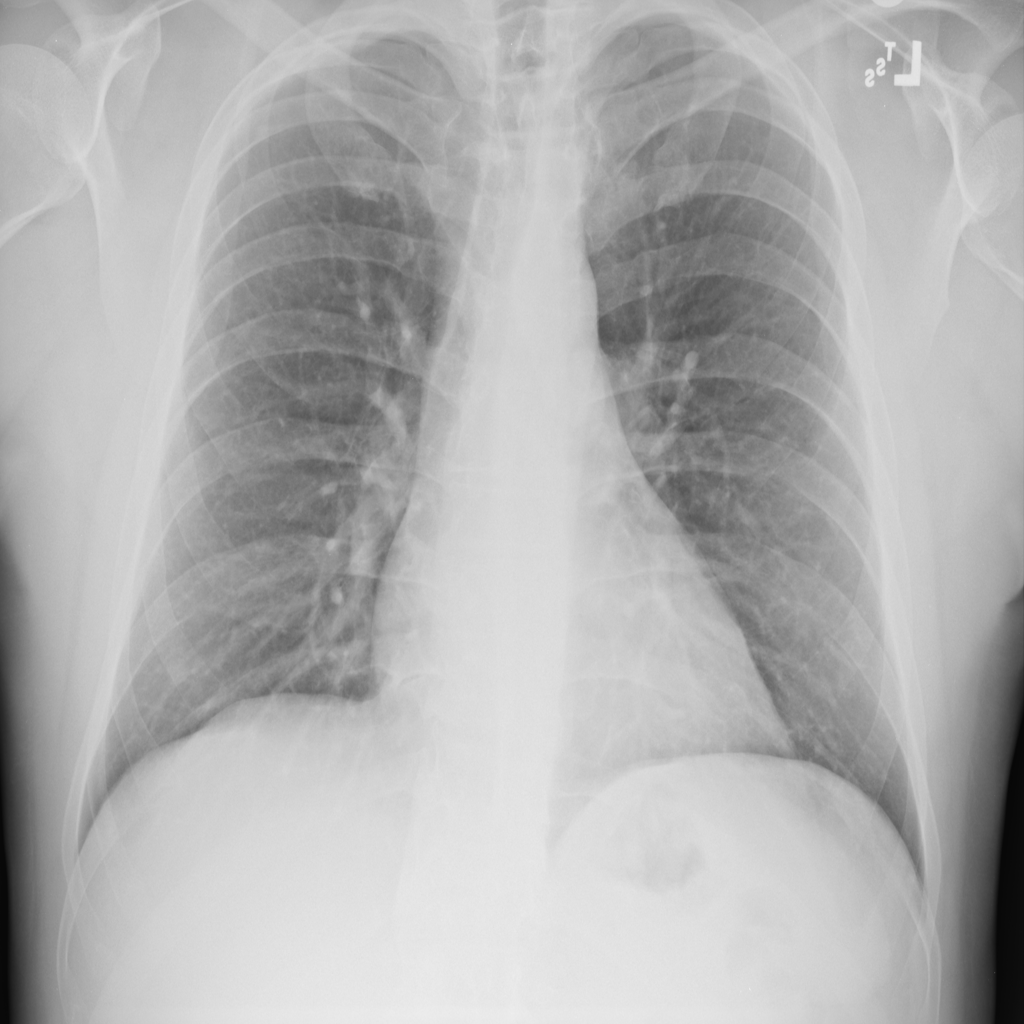

PAT-55FC · IMG-033Emphysema

PAT-55FC · IMG-033

AP